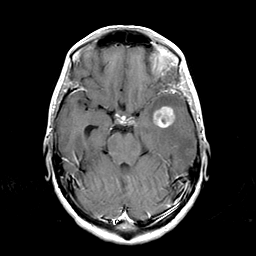

Metastatic bronchogenic carcinoma: T1-weighted MR -- Slice #7

[Home][Help][Clinical] Slice 7